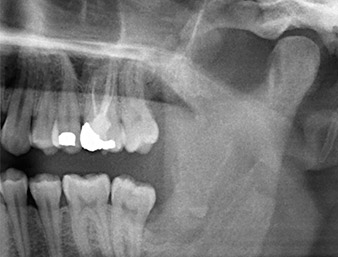

En la imagen en 3D (tomografía volumétrica digital) se constató que el resto radicular se encontraba muy desplazado en sentido distocaudal en la transición situada entre la porción horizontal y la ascendente del maxilar inferior (figura 2).